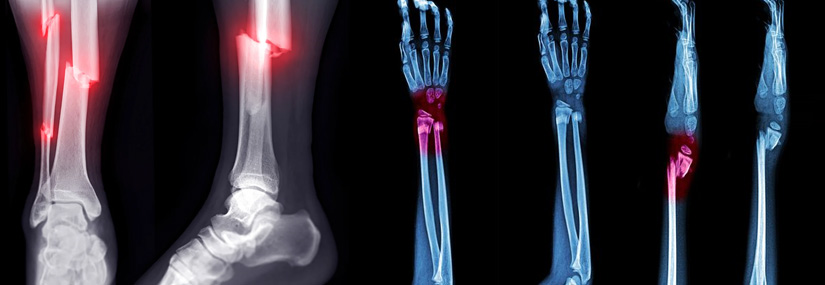

Compound Fracture

A compound fracture, also known as an open fracture, is a type of bone fracture in which the broken bone pierces the skin and is exposed to the external environment. This type of fracture is particularly serious because the exposure of the bone increases the risk of infection, both to the bone itself (osteomyelitis) and to surrounding tissues. Compound fractures typically result from high-energy trauma and require prompt and specialized medical treatment.